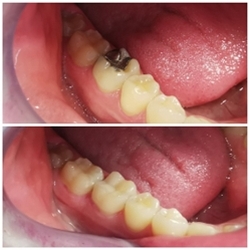

Opća dentalna medicina podrazumijeva prvenstveno restorativnu dentalnu medicinu. Ta grana dentalne medicine se bavi liječenjem i popravljanjem zuba oštećenog karijesom. Zubni karijes najčešća je bolest zubi današnjice, pa je tako terapija ispunom (plombom) najčešći zahvat u ordinaciji dentalne medicine. Karijes je propadanje zubne cakline i dentina uslijed djelovanja bakterija. Obično se pojavljuje u područjima teško dostupnima čišćenju ili koja zanemarujemo. Bakterije se nakupljaju na različitim površinama zuba, koriste šećer iz hrane i stvaraju kiselinu koja počinje nagrizati caklinu i prodirati sve dublje u zubno tkivo.

Svaki zub je dragocjen te se trudimo provoditi minimalno invazivne postupke kada god je to moguće. Današnji materijali za ispune oponašaju boju zuba, ne zahtijevaju mnogo brušenja strukture zuba i dovoljno su čvrsti da zamijene dio oštećen karijesom.

Nakon uklanjanja karijesa, zdrave dijelove zuba punimo kako bi zub zadržao vitalitet i funkciju. Ispuni mogu varirati od klasične plombe do modernih keramičkih ispuna (tzv. inlay i onlay ispuni) koji su trajnija, otpornija i estetski najprihvatljivija vrsta ispuna.

U našoj ordinaciji koristimo najbolje kompozite i adhezivne sustave (kojima se kompozit „lijepi“ za zub), te radimo sve navedene tretmane čišćenja kamenca, te pjeskarenja kao i floridacije zuba.